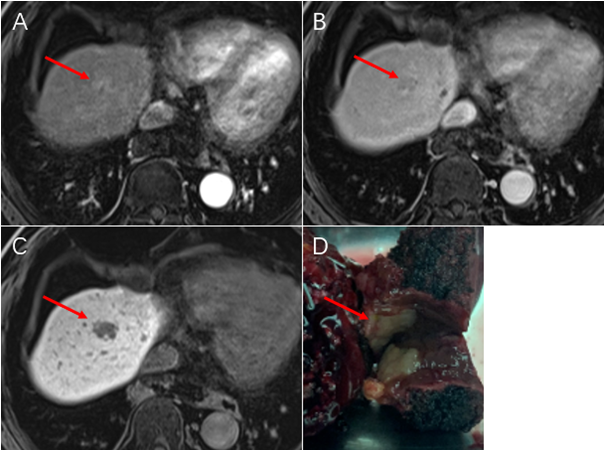

患者,女,59岁,肝细胞肝癌,5-10年前有子宫内膜癌、乳癌。

患者经过三次cTACE,随访3年,肿瘤持续缩小,无强化。

术前TACE,利于肿瘤切除。

术后病理证实无存活肿瘤,随访十一年健康生存。

术后TACE ,治疗术后复发。